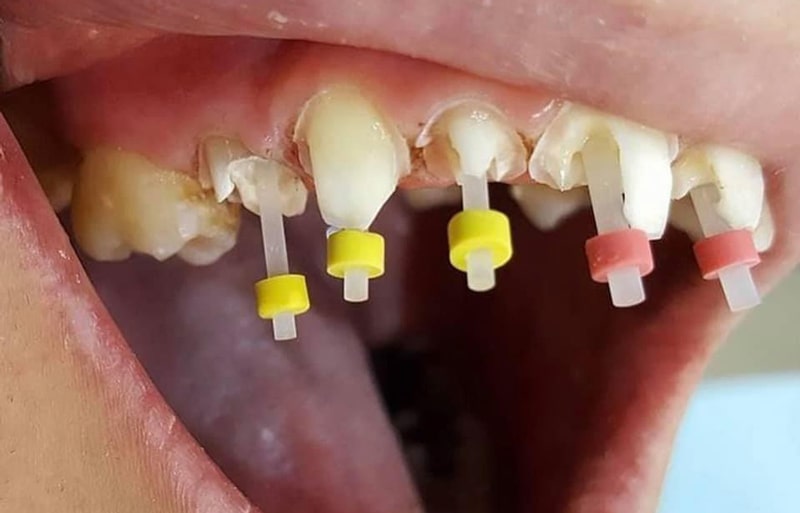

پست دندانی معمولاً زمانی مورد استفاده قرار می گیرد که دندان دچار تخریب شدید تاج شده، اما ریشه آن هنوز سالم و محکم است؛ این مشکل معمولاً پس از درمان ریشه (عصب کشی) به وجود می آید؛ یعنی بخش تاج از بین رفته اما می توان از ریشه، جهت نگهداری ساختار جدید استفاده کرد.

پست دندانی برای دندان های عقب دهان که فشار جویدن زیادی را تحمل می کنند، گزینه ای کاربردی و نسبتاً اقتصادی است؛ اگر هنوز دندان تان قابل نجات است و نمی خواهید وارد درمان های گران تر مثل ایمپلنت شوید، استفاده از پست دندان برای کاشت یک میله نازک فلزی یا فیبری در ریشه دندان و سپس استفاده از روکش دندان برای نصب تاج روی پایه و تقویت دندان، بهترین انتخاب برایتان خواهد بود.

با این حال، درصد موفقیت این روش به سلامت کامل ریشه و عدم وجود عفونت یا شکستگی در پایه دندان بستگی دارد؛ در صورت وجود مشکل جدی در هر یک از این بخش ها، ممکن است پست و روکش دندان باعث آسیب به ریشه شوند.

- بعد از عصبکشی: 1 جلسه نصب پست

- قالبگیری روکش و ساخت آن: 1 تا ۲ هفته

- نصب نهایی روکش: 1 جلسه

در مجموع: حدود ۷ تا ۱۴ روز زمان می برد.

در مقابل، اگر ریشه دندان سالم باشد و فقط ساختار تاج دندان آسیب دیده باشد، نیازی به کشیدن دندان نیست و می توان دندان طبیعی را حفظ کرد؛ برای این کار، دندان پزشک از روش پست و روکش استفاده می کند؛ در این روش، دندان پزشک یک پایه نازک فلزی را در بخش ریشه دندان کاشته و یک تاج را روی آن قرار می دهد. به صورت میانگین، پست و روکش دندان در سال ۱۴۰۴، هزینه ای در حدود ۳ تا ۱۱ میلیون را در پی دارد.